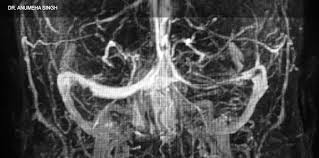

Common subtypes include transverse sinus thrombosis and superior sagittal sinus. What causes cerebral venous sinus thrombosis? Magnetic resonance imaging of cerebral venous sinus thrombosis. Aha scientific statements ⅲ venous thrombosis ⅲ sinus thrombosis, intracranial ⅲ brain infarction figure 1. Cerebral venous sinus thrombosis in early pregnancy: The cavernous sinus is one of the several cerebral veins and cavernous sinus thrombosis is a specific type of cerebral venous (sinus) thrombosis. Cerebral venous thrombosis (cvt) or cerebral venous sinus thrombosis (cvst): Cochrane database syst rev 2011; Cerebral venous and sinus thrombosis (cvst) is a rare disease responsible for less than 1% from the total of avc causes (bajenaru, 2010). Thrombosis of cerebral veins and venous sinuses is a rare disease, which accounts for less than 1% of all cases of stroke. The venous circulation of the brain is done. Risk factors, presentation, diagnosis and outcome. See that article for a discussion of that specific clinical entity.

Magnetic resonance imaging of cerebral venous sinus thrombosis. (iii) clinical and radiological features of brain lesions in csvt compared with arterial stroke, and (iv) a low threshold for ct or mr venography in children with acute neurological symptoms is essential. Can cerebral venous sinus thrombosis be prevented? Thrombosis of cerebral veins and venous sinuses is a rare disease, which accounts for less than 1% of all cases of stroke. Cerebral venous thrombosis (cvt) is an uncommon disorder in the general population. A thrombotic obstruction of the cerebral veins and/or related anatomical structures (dural sinuses) which drain blood from the brain. Cerebral venous thrombosis accounts for less than 1 % of all cases of stroke worldwide. A case report and review of the literature. Cerebral venous and sinus thrombosis (cvst) is a rare disease responsible for less than 1% from the total of avc causes (bajenaru, 2010). Cerebral venous sinus thrombosis occurs when a blood clot forms in the brain's venous sinuses. Cerebral venous thrombosis (cvt) refers to occlusion of venous channels in the cranial cavity, including dural venous thrombosis, cortical vein although not used routinely in clinical practice, whole brain ct perfusion may assist in establishing the diagnosis of cvt by detecting perfusion. Common subtypes include transverse sinus thrombosis and superior sagittal sinus. Cerebral venous thrombosis (cvt) or cerebral venous sinus thrombosis (cvst):